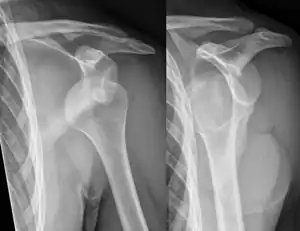

Lightbulb sign indicative of posterior shoulder dislocation shown on the left. On the right, the same shoulder after reduction.

Posterior dislocations are uncommon, and are typically due to the muscle contraction from electric shock or seizure.[6] They may be caused by strength imbalance of the rotator cuff muscles. People with dislocated shoulders typically present holding their arm internally rotated and adducted, and exhibiting flattening of the anterior shoulder with a prominent coracoid process.

Posterior dislocations may go unrecognized, especially in an elderly person[12] and in people who are in the state of unconscious trauma.[13] An average interval of 1 year was noted between injury and diagnosis in a series of 40 people.[14]